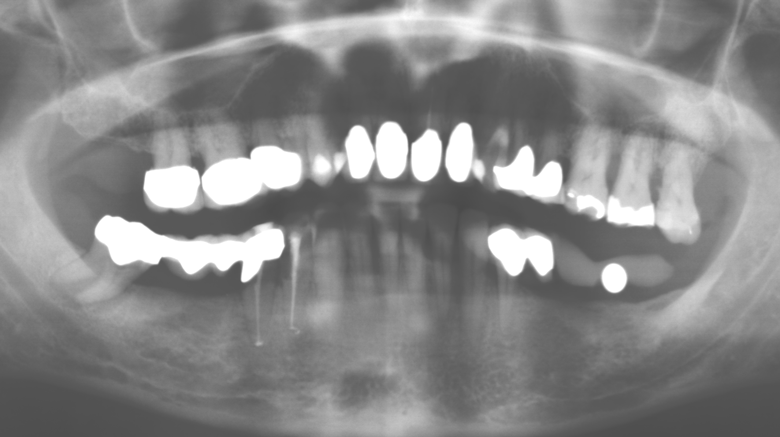

Un paziente di 52 anni si è presentato nella nostra clinica per la prima volta nel 2004 a seguito della perdita dei denti nel terzo quadrante, esprimendo il desiderio di un nuovo restauro protesico. La diagnostica parodontale e radiologica ha rivelato la necessità di un ampio trattamento parodontologico. Inoltre, ai denti 48, 28 e 27 è stata attribuita una prognosi molto scarsa e sono stati successivamente estratti (Fig. 1). A seguito del trattamento periodontologico sistematico completato con successo, è stato inserito una protesi dentale fissa con l'inserimento di cinque impianti nelle regioni dentali 35, 36, 37, 46 e 47. Il trattamento protesico dei denti naturali è stato effettuato con corone rivestite in ceramica di biossido di zirconio; gli impianti two-piece composti da abutment singoli in biossido di zirconio e corone similmente rivestite in ceramica di biossido di zirconio (base Cercon colorata, Dentsply Sirona Lab). L'inserimento definitivo del restauro protesico è avvenuto nel 2005.

Il controllo decennale non ha rivelato alcuna indicazione dell'avanzamento della perdita di attaccamento clinico o della perdita di sostanza ossea perimplantare (Fig. 3).